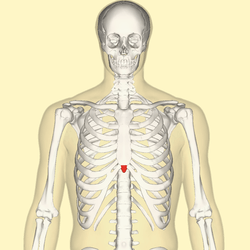

Position of the xiphoid process (shown in red). | |

Position of xiphoid process (shown in red). Animation.

Position of xiphoid process (shown in red). Animation. Close up.